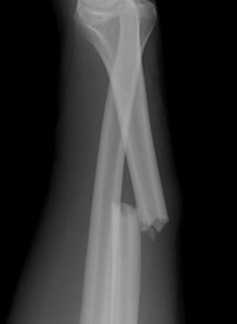

Форма линии перелома

Переломы подразделяют и по линии повреждения костных тканей. Травма может быть:

При поперечных переломах травма считается стабильной. Смещения отломков кости чаще всего не происходит. В остальных случаях кость после травмы смещается, так как ее тянет мышечная ткань.

Оскольчатый вид перелома характеризуется отделением от кости одного или нескольких острых осколков, которые попадают в мягкие ткани. При таком повреждении больному понадобится хирургическое вмешательство и длительный реабилитационный период. Такая травма может быть крупно- и мелкооскольчатой.

Здесь можно выделить следующие типы переломов:

- Поперечные,

- косые,

- продольные,

- винтообразные,

- окольчатые,

- клиновидные

Все эти переломы проиллюстрированы на картинке ниже: